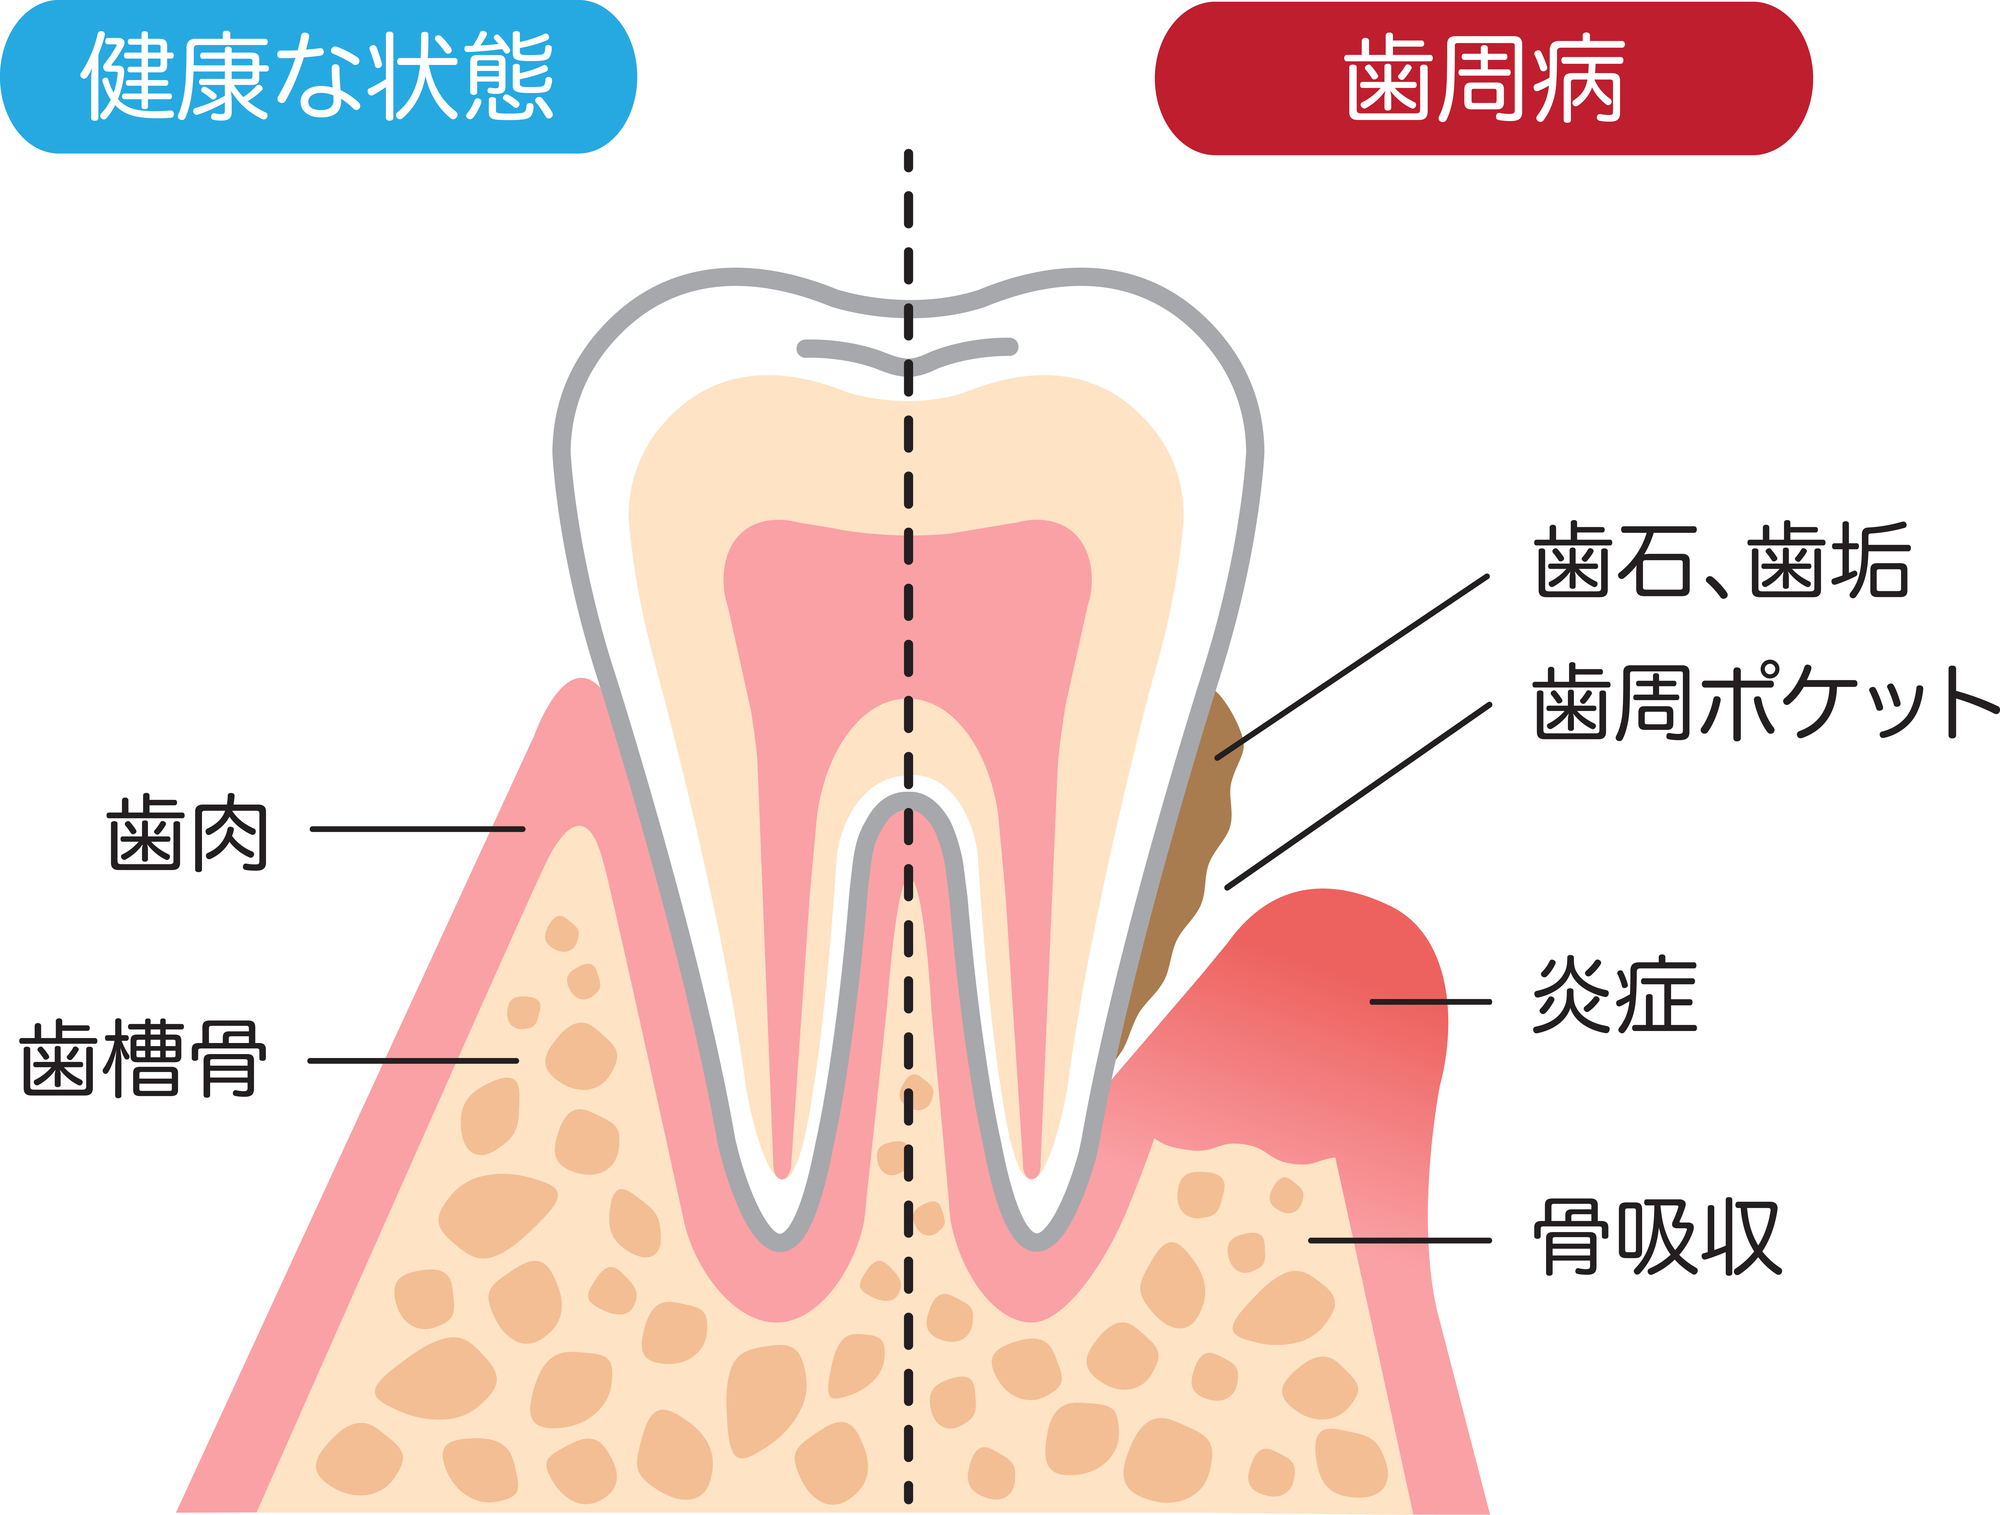

歯周病とは、歯を支えている歯槽骨が溶けていく病気です。

歯周病になると、歯茎や歯肉の張りは失われ退縮していきます。それによって、歯が動き隙間ができたり、歯と歯茎の間にある歯周ポケットと呼ばれる細い溝がどんどん深くなっていき、その部分に食べ物が詰まりやすくなってしまいます。

歯周病もひどく悪化すると、全身の健康に影響を及ぼす病気です。早期発見・早期治療のためにも、定期的に歯科検診を受けましょう。